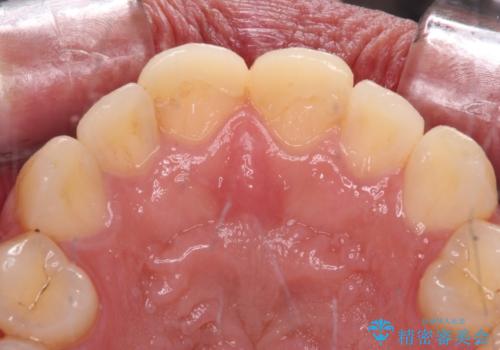

- 自転車で転んで前歯をぶつけたとのことで来院された患者様です。

事故後に受診した病院の歯科にて前歯2本の欠損した部分を修復されておりましたが、見た目が気になるとのことで、オールセラミッククラウンにて補綴治療を行うこととしました。

神経組織の状態を確認しましたが、片方は正常反応でしたが、他方は鈍い反応しかありませんでした。

速やかにオールセラミッククラウンにて補綴治療を行い、数ヶ月後に再度神経組織の状態を確認して、失活しているようであれば根管治療を行うこととしました。